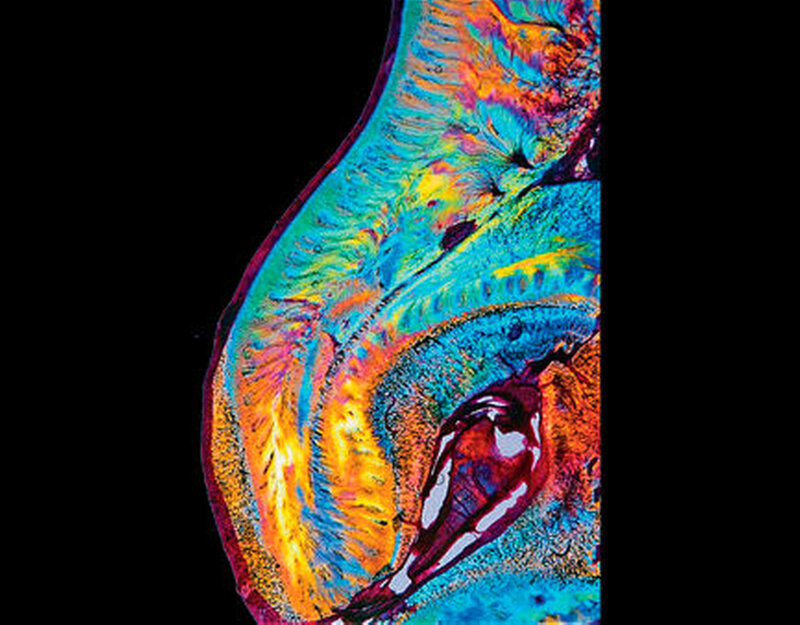

Zuerst bilden die vorhandenen Odontoblasten normales Dentin. Später werden die Odontoblasten zunehmend durch mesenchymale Zellen ersetzt, welche atypisches Dentin mit irregulär verlaufenden Dentintubuli bilden (Abbildungen 7a, b und 9). Die Dentinogenesis imperfecta führt zu einer blaubraunen Verfärbung der Milchzähne und zu einer bernstein-/perlmuttartigen Verfärbung der permanenten Zähne (Abbildungen 5, 6a,b und 8). Das vorhandene Dentin ist weicher als normal. Die histologischen Schnitte zeigen eine oft wellige Schmelz-Dentin-Grenze, was auf einen Defekt des Schmelz-Dentinverbundes schließen lässt (Abbildung 10). Infolge der mangelhaften Schmelz-Dentinverbindung splittert häufig Schmelz ab. Diese Schmelzabsplitterungen können zu Kariesbildung an atypischer Lokalisation führen (Abbildungen 6a, b). Zudem unterliegen die Zähne einer erhöhten Attrition. Irreguläre Dentinbildung kann nach dem Zahndurchbruch die gesamte Pulpakammer obliterieren. Beim gleichen Patienten können jedoch vollständig obliterierte neben normalen Pulpakammern beobachtet werden.